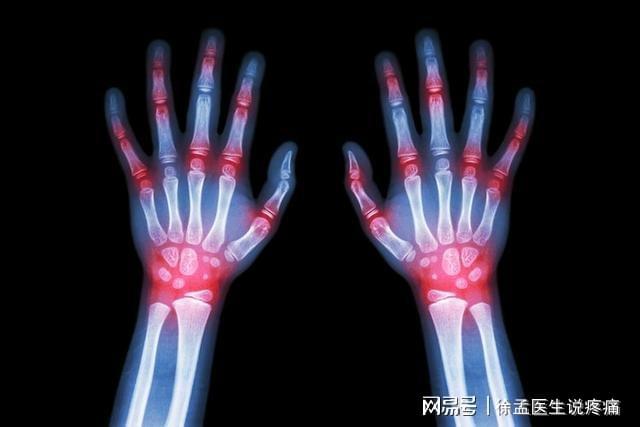

4. 진단을 확인하기 위해 필요한 경우 관절 X-ray를 찍거나 다른 검사를 하십시오.